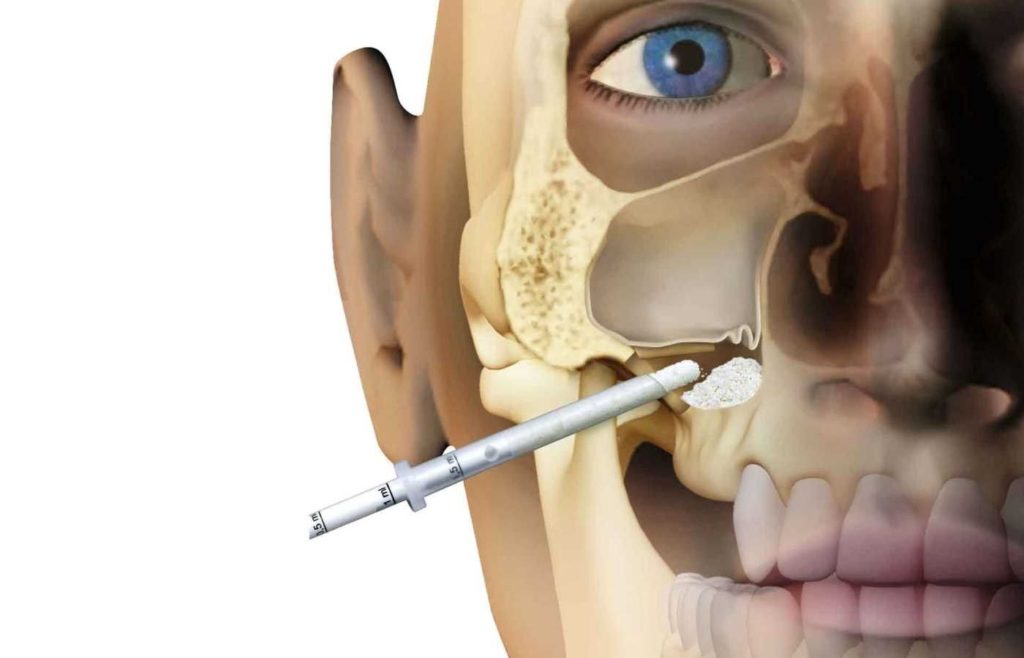

دندان عقل، به ویژه در فک بالا، در نزدیکی سینوس فکی قرار دارد؛ به همین دلیل، در صورت بروز نهفتگی ممکن است مشکلاتی فراتر از دهان و دندان ایجاد کند. خطر دندان عقل نهفته در سینوس یکی از عوارض کمتر شناخته شده اما جدی است که می تواند باعث درد، التهاب، عفونت و حتی اختلال در تنفس شود. این مشکل زمانی رخ می دهد که ریشه های دندان عقل به سینوس نزدیک باشند یا در اثر فشار و التهاب، دیواره سینوس آسیب ببیند.

در فک بالا، ریشه های دندان عقل به سینوس فکی بسیار نزدیک اند و در برخی افراد حتی با دیواره سینوس تماس مستقیم دارند. در چنین شرایطی، نهفتگی دندان می تواند باعث فشار یا التهاب در ناحیه سینوس شود.

تشخیص این حالت تنها با بررسی تخصصی و رادیوگرافی پانورامیک یا سی تی اسکن امکانپذیر است تا میزان درگیری سینوس مشخص شود. درمان به موقع از گسترش عفونت به سایر بافت های صورت جلوگیری می کند.

درمان دندانی که در مجاورت سینوس قرار دارد نیازمند دقت بالایی است و حتما باید زیر نظر متخصص انجام شود. دکتر ساره نادعلی زاده، به عنوان بهترین متخصص دندانپزشکی کودکان غرب تهران، با بهره گیری از تجربه بالینی و دانش تخصصی خود، قادر است با استفاده از تصاویر رادیوگرافی دقیق، موقعیت دندان عقل را نسبت به سینوس بررسی کند.

تشخیص درست پیش از جراحی از اهمیت بالایی برخوردار است، زیرا در صورت دستکاری نادرست ممکن است دیواره سینوس سوراخ شود و مشکلاتی مانند نشت هوا یا عفونت ایجاد گردد. دکتر نادعلی زاده با روش های کم تهاجم و تجهیزات مدرن، خطرات احتمالی را به حداقل میرساند و فرآیند درمان را با ایمنی کامل انجام می دهد. انتخاب متخصصی باتجربه، کلید اصلی در جلوگیری از عوارض جدی مرتبط با دندان عقل نهفته در سینوس است.